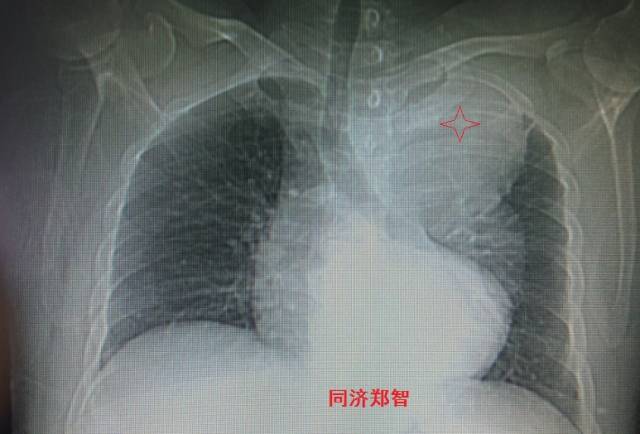

病例一

胸片提示左上纵隔影增宽(红色星形标记),CTA证实B型主动脉夹层伴降主动脉夹层动脉瘤形成。

图1-2